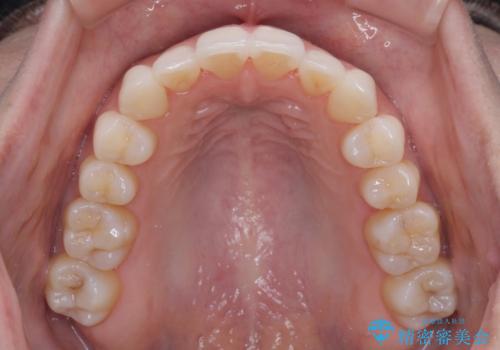

前歯のクロスバイト インビザラインによる矯正治療

- 上下のクロスバイトと前歯のデコボコを気にして来院された患者様です。

インビザラインを用い、IPR(歯と歯の間を削る)と歯列全体を拡大させることで、歯並びを整えていくこととしました。

治療を急いでいらっしゃらなかったため、のんびりと治療を進めていきました。3年以上の期間を要しましたが、きれいな口元に仕上がりました。